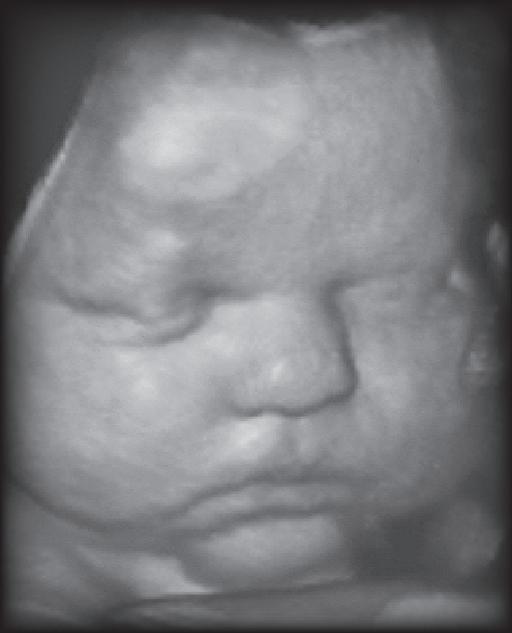

KVT: Does breast-feeding babies affect their weight later in life?

LF: Yes. Breast-feeding has been associated with preventing excess weight gain. It’s felt that breast-fed babies are better able to control their intake and follow their own internal hunger cues versus those who are given a fixed quantity of milk or formula in a bottle. It’s believed that breast-fed babies develop a better sense of when they’re full.